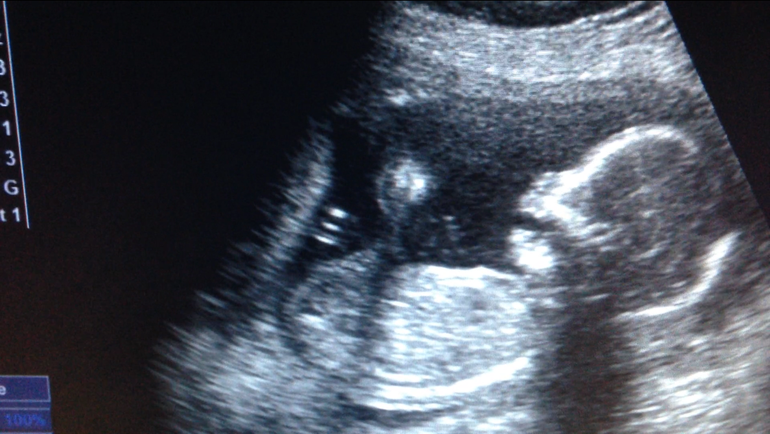

Загоняюсь или что-то не так с нижней челюстью?

Страхи, переживания и немножечко нытьяУзист ничего не сказал, а я только на фото увидела, прям режет глаз мне эта челюсть. У старших детей посмотрела: красивый профиль с нормальным подбородком. А тут не пойму ракурс такой, и рот открыт может..может у кого были такие картинки? :)

Тоже такой загон был,а потому что на узи у него был открыт рот,так и засняли и я прям переживала,что какой-то разрез рта большой,на втором скрине было и зд,все отлично со ртом))вот это фото) и он на всём видео такой,видимо глотал воды)

єто просто на такой длине волны фотка сделана))) Узи оно же как мрт , типа как слоями быстро картинку передает. Вот сейчас видно щечку, датчик приближает и уже визуализируется челюсть, по такому принципу и видно же и внутренние органы и внутренности внутренних органов)))

На фото глотал, да еще и слой кожи уже миновали, видны именно уже кости черепа